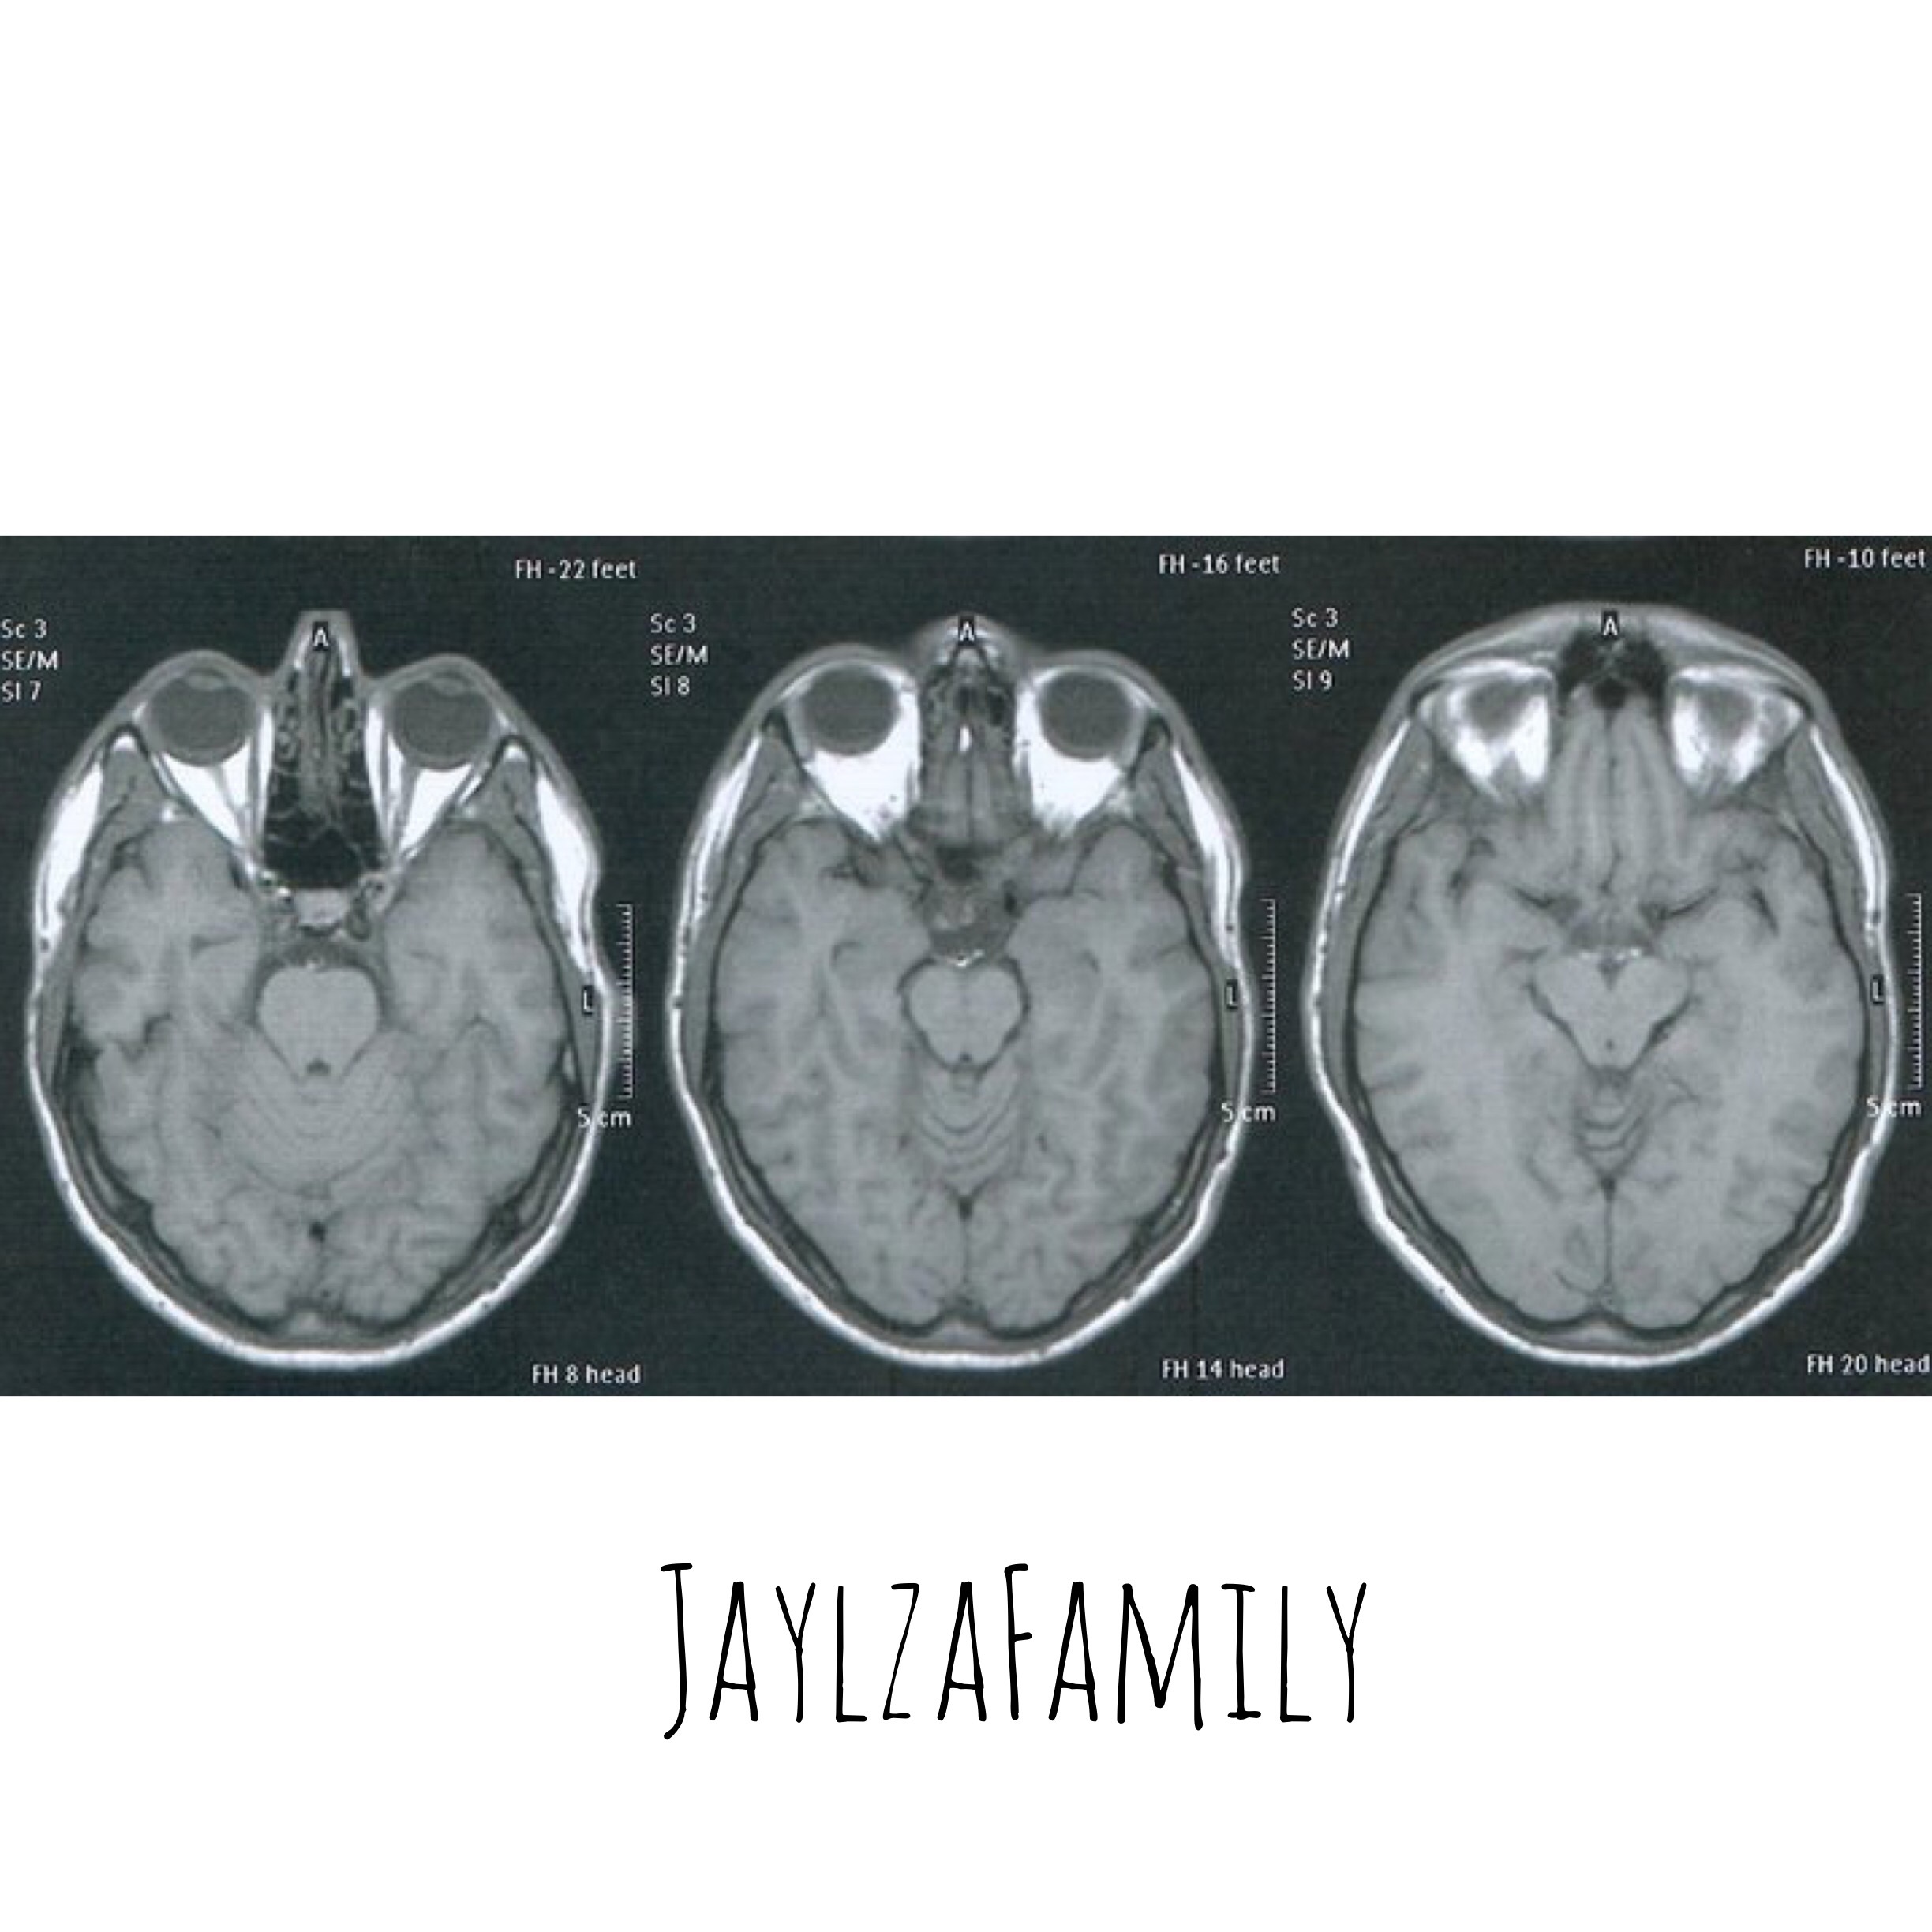

Et la Sclérose en Plaques se définit comme une maladie inflammatoire démyélinisante du système nerveux central.

Pour Papa Jay, la SEP se traduit par des névrites optiques. En gros, il voit avec un voile blanc, ou des zones noires, et bien sûr de bonnes douleurs ophtalmiques!